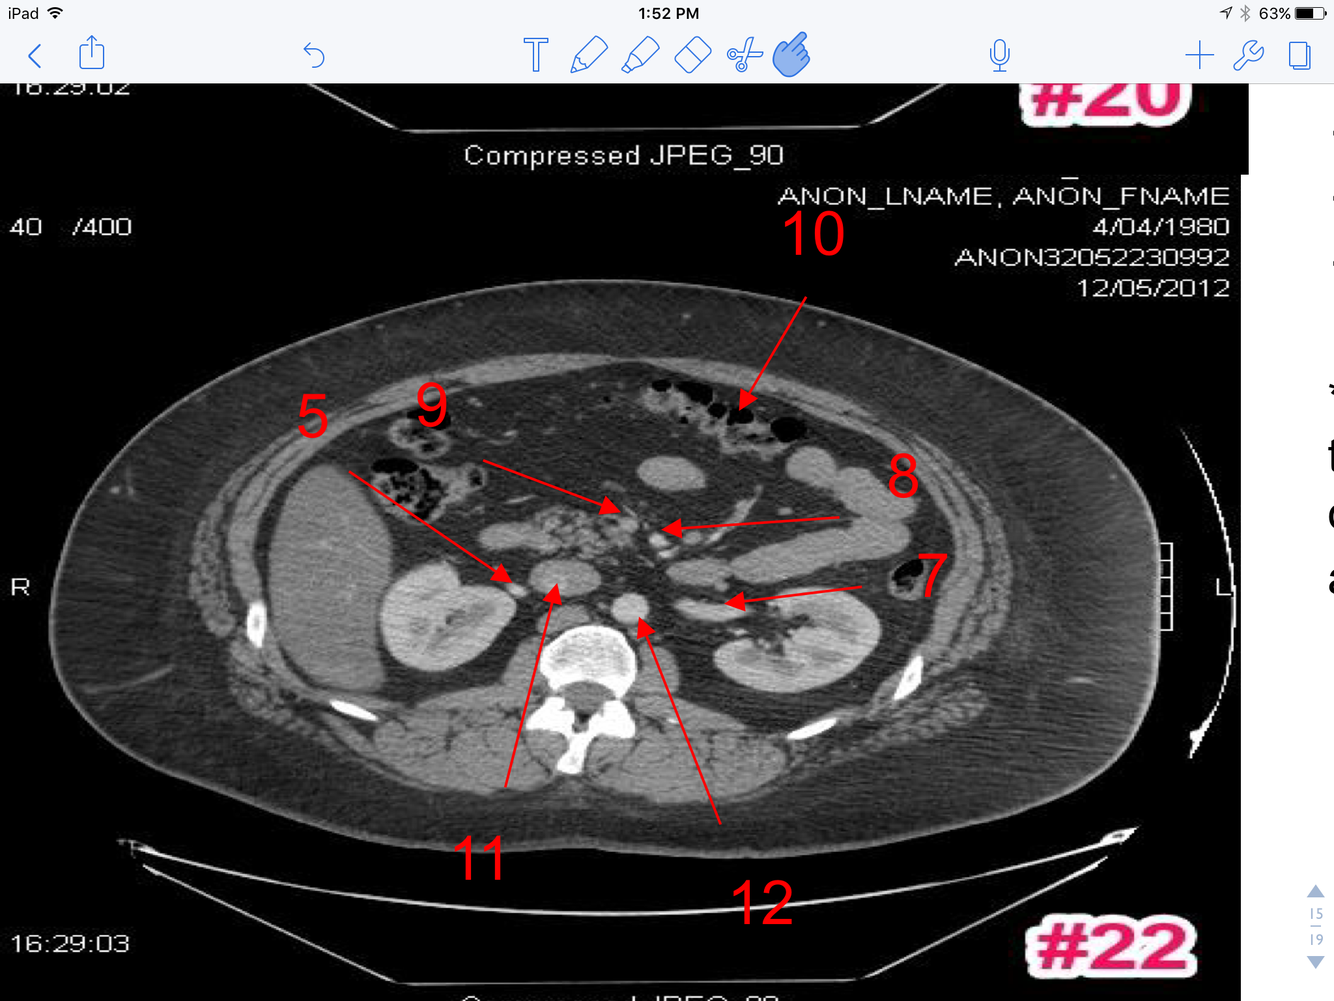

10

A

1. Lt Adrenal Gland

2. Splenic Artery

3. Celiac axis (trunk)

4. Rt. Adrenal

11

1. Fundus of the gallbladder

2. Uncinate process of pancreas

3. Portal Vein

4. Splenic Vein

5. Upper Pole of Lt Kidney

6. Superior mesenteric artery

12

1. Superior mesenteric artery

2. Superior mesenteric vein

3. Lt. renal vein

4. Rt. renal artery

5. Upper pole right kidney